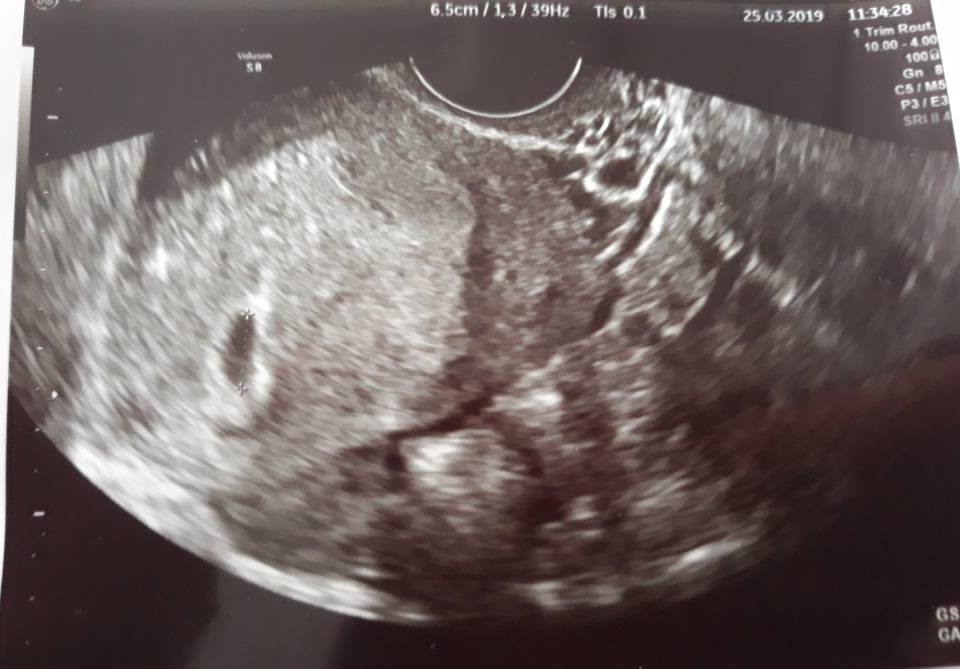

Hej dziewczyny, byłam dzisiaj u ginekolog. Zapisała mi jeszcze duphaston i luteine. Pęcherzyk ciążowy jest. Plamienie nie wydaje się być zagrożeniem. Kolejna wizyta za tydzień [emoji4]

Dzisiaj 5t6dc... 6.5mm podobno kilka dni młodszy, ale wydaje mi się, ze owulacje miałam dosyć później (ok. 19dnia cyklu)

20190325_114847.jpeg

Dzisiaj 5t6dc... 6.5mm podobno kilka dni młodszy, ale wydaje mi się, ze owulacje miałam dosyć później (ok. 19dnia cyklu) Zobacz załącznik 955478